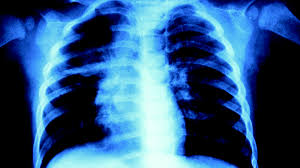

How To Check If You Have Lung Cancer - What Are The Signs And Symptoms Of Lung Cancer Branton12b2016s2 - This test is more likely to help find cancers that start in the major airways of the lung, such as squamous cell lung cancers.. The best way to prevent lung cancer. There are many different types of growths that can form in the lungs, and how they're diagnosed and treated depends on what symptoms you're having; The best way to do this is to get early morning samples 3 days in a row. For more guidance about lung cancer stages, see this post! A sample of sputum (mucus you cough up from the lungs) is looked at in the lab to see if it has cancer cells.

Lung Cancer Medlineplus Genetics from medlineplus.gov The best way to do this is to get early morning samples 3 days in a row. If the cancer has found in two lungs! What tests will doctors have to perform? A cancer may also cause symptoms like fever, extreme tiredness (fatigue), or weight loss. Diagnostic tools for lung cancer your doctor may use a variety of tests and scans to look for the presence of lung cancer. A biopsy is a procedure in which the doctor removes a sample of tissue. Low dose ct scan (low dose computed tomography scan) It is often the first imaging test a doctor will order if lung or heart disease is suspected.

Doctor Goes Through Ten Signs That Suggest You Don T Have Cancer from cf-images.eu-west-1.prod.boltdns.net A cancer can grow into,or begin to push on nearby organs, blood vessels, and nerves. It is often the first imaging test a doctor will order if lung or heart disease is suspected. A ct scan (computed tomography scan) alone may not be enough to confirm or rule out lung cancer. A biopsy is a procedure in which the doctor removes a sample of tissue. Your doctor may recommend imaging tests, sputum cytology or a tissue sample, called a biopsy. Where the growths are in the lung; The scan only takes a few minutes and is not painful. See a doctor if your cough lasts more than 2 weeks, if it increases in intensity over time, or if you cough up blood (this is called hemoptysis) or a lot of phlegm.